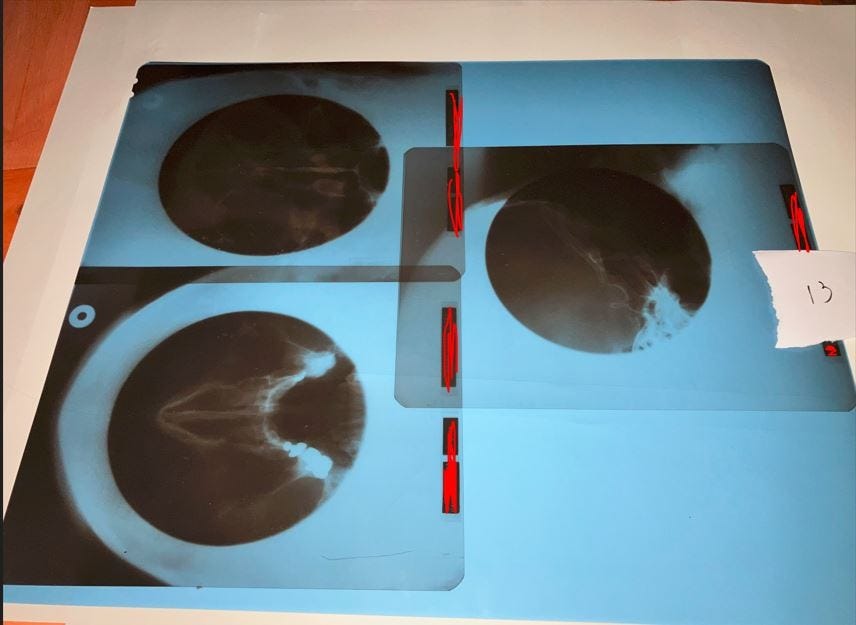

Kuva 13: nenä ja kalloa. Koko 43 x 35 cm, leikattu kuvan ottamisen jälkeen kahteen osaan punaisella merkityn alueen kohdalta potilastietojen poistamisen yhteydessä.